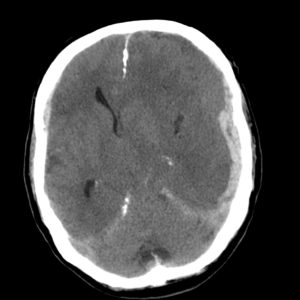

Медицинские аспекты и диагностика субдуральной гигромы мозга